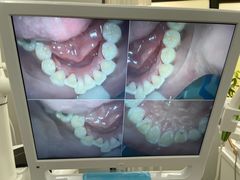

• 牙博士口腔品牌连锁(杨浦店)

• -牙博士口腔品牌连锁(杨浦店)